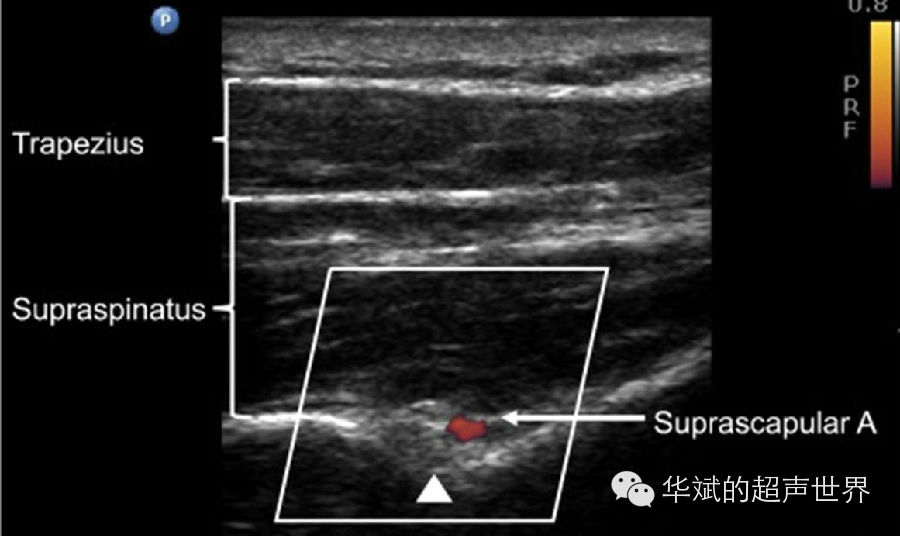

1. 以骨性结构作为标志(表三)。某些外周神经常常临近一些特定骨性解剖部位,超声检查时通过寻找这些骨性标志就可以定位具体的神经。例如:腓总神经在腘窝上缘自坐骨神经分出后向外绕过并紧贴腓骨颈向前向下再分出腓浅神经和腓深神经。因此,我们可以将腓骨颈作为定位腓总神经的重要标志(图7)。又如:肩胛上神经走形于冈上肌深方肩胛骨的肩胛上切迹内,超声检查时只要显示肩胛上切迹就可以定位肩胛上神经(图8)。

8 肩胛上神经定位。于冈上窝扫查,探头大致与肩胛冈平行。三角箭头:肩胛上切迹肌其内的肩胛上神经,Suprascapular A:肩胛上动脉,Supraspinatus:冈上肌,Trapezius:斜方肌

事实上,大多数的外周神经都可以综合利用血管、肌肉和骨骼作为标志来定位。例如,肩胛上神经除了肩胛上切迹骨性标志外,同时还可以以临近的肩胛上动脉作为定位标志(图8)。而阴部神经则可以同时以坐骨棘和阴部动脉作为定为标志(图4)。我们在实际工作中要熟悉各条外周神经在不同位置的毗邻血管、肌肉和骨骼,综合应用这些解剖标志,使我们对神经的定位更加准确高效。